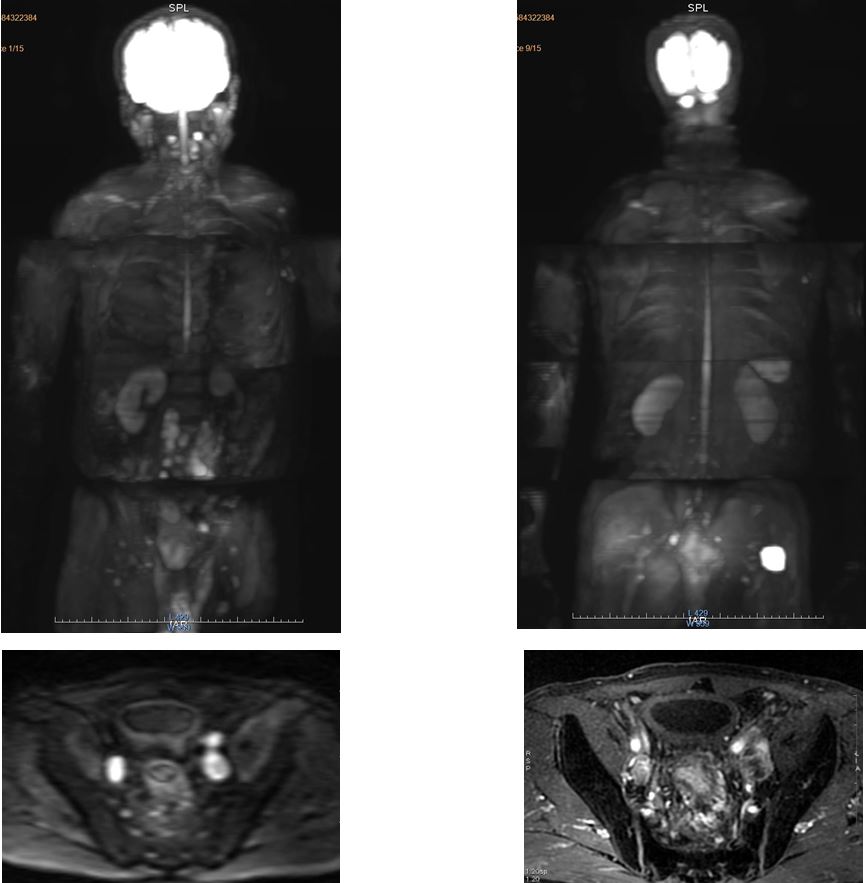

Một số hình ảnh thực tế:

Hình ảnh chụp cộng hưởng từ toàn thân trên bệnh nhân ở Hubet com cá cược thể thao 108

Phát hiện Hubet8000.com Casino & Thể Thao Link Mới trực tràng di căn hạch trên cộng hưởng từ toàn thân